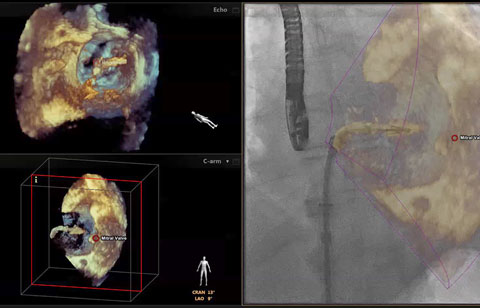

بعد تشخيص مريض بارتجاع الصمام الميترالي، ما هي خيارات العلاج المتوفرة له؟ إذا لم يكن مرشحًا للخضوع لعملية القلب المفتوح، يمكنك التفكير في معالجته عبر إصلاح الصمام الميترالي باستخدام القسطرة (TMVR). وفي يومنا الحالي، تؤمن حلول التصوير المبتكرة والأجهزة المتوفرة حديثًا خيارات جديدة لبعض المرضى.

التخطيط للإجراءات باستخدام البيانات الكمية الموثوقة.

متابعة إجراءات التدخل وتقييمها من خلال الاتصالات الموسّعة بين أعضاء فرق طب القلب.